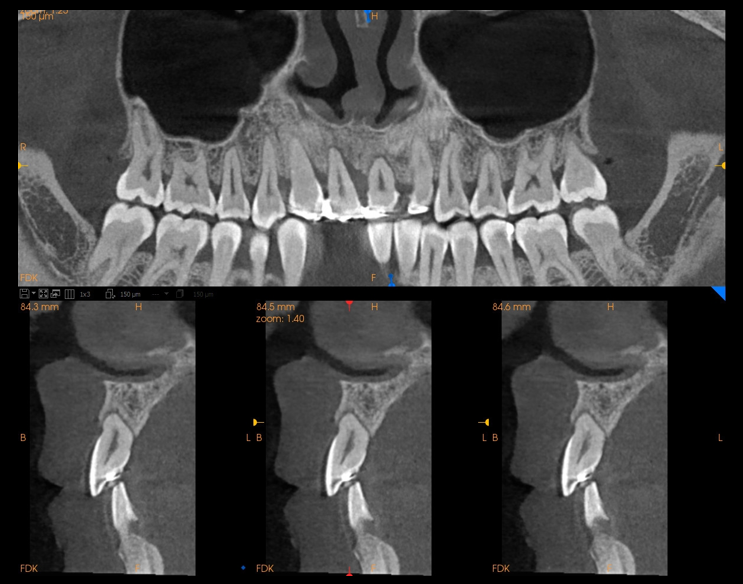

Endodoncja (leczenie kanałowe)

zdjęcie tomograficzne szczęki